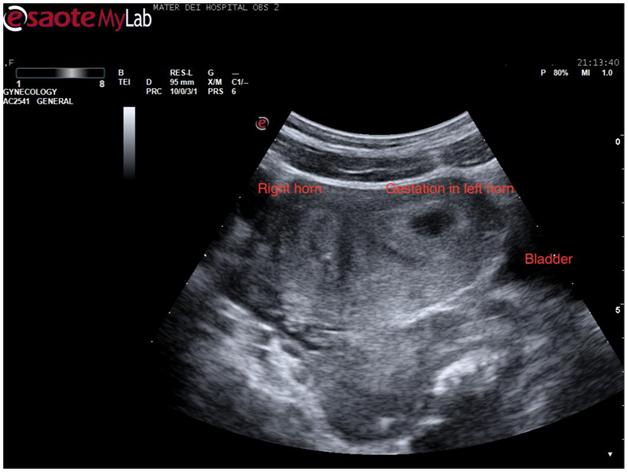

At this stage a decision was made to proceed to transvaginal scan in the hope of mapping the coils’ location better. Once again verbal consent was obtained and after covering the patient with a modesty sheet the high-frequency endovaginal probe was gently introduced after covering with gel and a probe cover. The images obtained confirmed the findings of the abdominal scan (Figure 5). By rotating the probe anticlockwise the uterus could be visualised in its transverse diameter. This view is a good one for demonstrating separation of the endometrial stripe into 2 as the uterus is scanned from a caudal to a cephalic direction. On reaching the fundus 2 definite horns are usually visualized (Figure 6). In this case, a gestation sac was distending the left horn as demonstrated in Figure 7. The rest of the examination was normal with both adnexae visualised and appearing normal.

Figure 7 Transvaginal scan showing a transverse view of the uterine fundus with 2 separate horns.